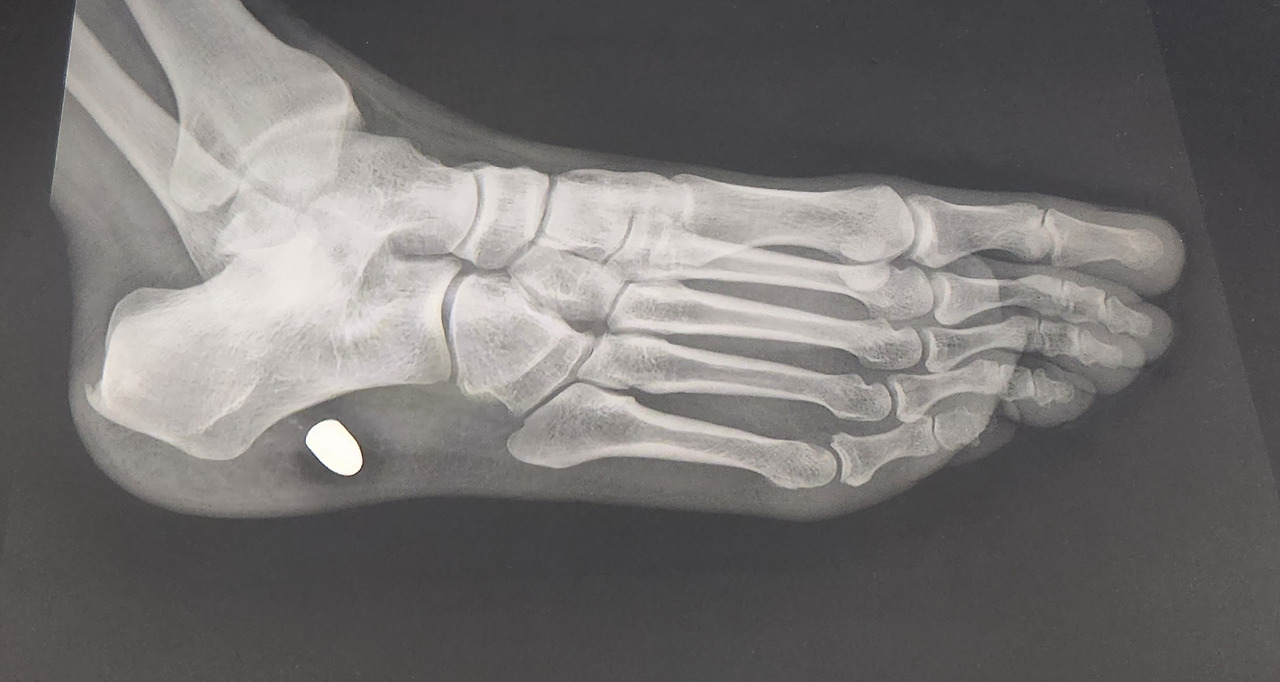

“어… 이게 뭔가요? 엑스레이 사진에 총알 같은 게 보이는데요?”

의사의 말에 내 머릿속은 하얗게 비어버렸다. 총알? 내 발에, 총알이 박혀있다고? 4개월 전, 이스탄불의 그날 밤이 섬광처럼 스쳐 지나갔다.

그리고 마침내 돌아온 한국의 병원. 엑스레이 사진 속, 내 발뒤꿈치 뼈 옆에 선명하게 박혀있는 38구경 권총탄 추정 물체. 의사의 말을 듣는 순간, 지난 4개월의 고통과 사투가 퍼즐처럼 맞춰졌다. 나는 경악을 금치 못했다. 이런 걸 발에 넣고 그 험한 길을 계속 걸어 다녔다니.